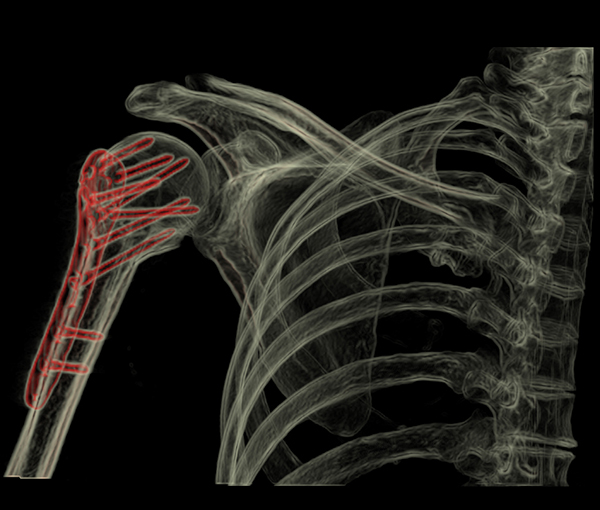

ATTENTION à la charnière dorsolombaire compter les vertèbres Attention La radio du thorax n’est pas une radio du rachis Rachis lombaire rappel anatomique SCANNER 4 COUPES DE BASE SOUS PEDICULAIRE DISCALE SUS PEDICULAIRE PEDICULO CORPOREALE SCANNER MULTI BARETTE BODY SCAN • PB POLYTRAUMATISE.